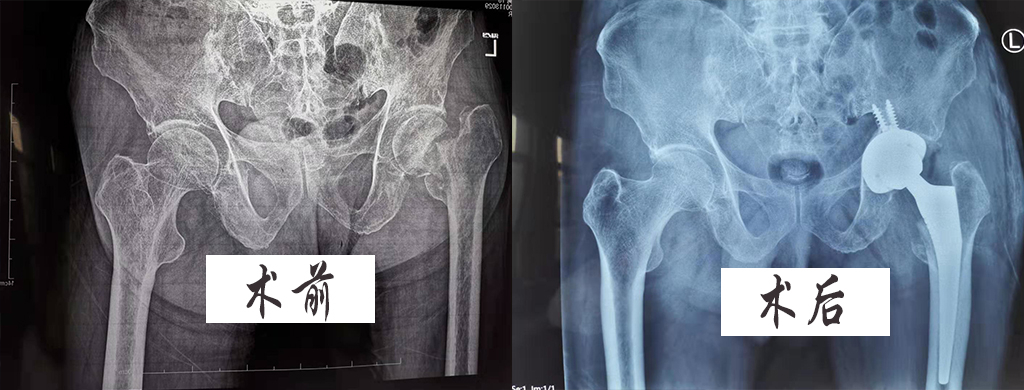

原來患者曾先生,在年初旅游時不慎摔傷左髖部,據(jù)家屬介紹:在當(dāng)?shù)蒯t(yī)院X線片檢查后為“左股骨頸骨折”,當(dāng)時并未住院治療,僅在家保守治療,期間未看到明顯好轉(zhuǎn),再后來X線片檢查“左股骨頸陳舊性骨折,未愈合,下肢明顯短縮”,并伴有夜間疼痛,一直臥床不能行走等情況。

患者曾先生為一大學(xué)教授,研究生導(dǎo)師,左髖部疼痛嚴(yán)重影響他的身體活動和生活質(zhì)量,今特選我院尋求進(jìn)一步治療,我院遂以“左股骨頸陳舊性骨折”收入院,急診外科張魁林主任為其主治醫(yī)生。

在經(jīng)過專業(yè)詳細(xì)的體格檢查、??茩z查、輔助檢查后,初步診斷為“1、左股骨頸陳舊性骨折2、左側(cè)股骨頭壞死3、類風(fēng)濕性關(guān)節(jié)炎”情況,在完善檢查排除手術(shù)禁忌后,準(zhǔn)備給予“做人工股骨頭置換術(shù)+髖關(guān)節(jié)滑膜切除術(shù)”。

在征得家屬同意后,于2019年11月21日在麻醉科的會診下進(jìn)行了手術(shù),術(shù)中術(shù)后順利,期間又給予了預(yù)防感染、消腫、抗凝等治療,曾先生于術(shù)后三日就可以在家人的協(xié)助下行走,家屬非常滿意,直到出院時曾先生一般情況,飲食、睡眠、大小便均正常,恢復(fù)較好。